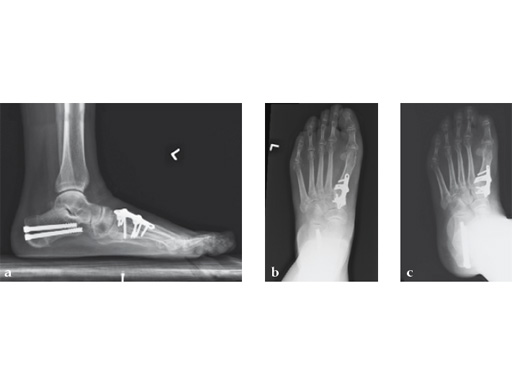

Case 3: First TMT fusion plate

A 48-year-old woman, with hallus valgus and hypermobile medial column, also resulting in pes plano abductovalgus (flatfoot).

Case provided by Andrew Sands, New York, New York, USA

Surgery consisted of first TMT and intertarsal corrective osteotomy plus fusion with movement of the first MT lateral and plantar. This corrects the hallus valgus as well as the PPAV (and stabilizes the medial column).